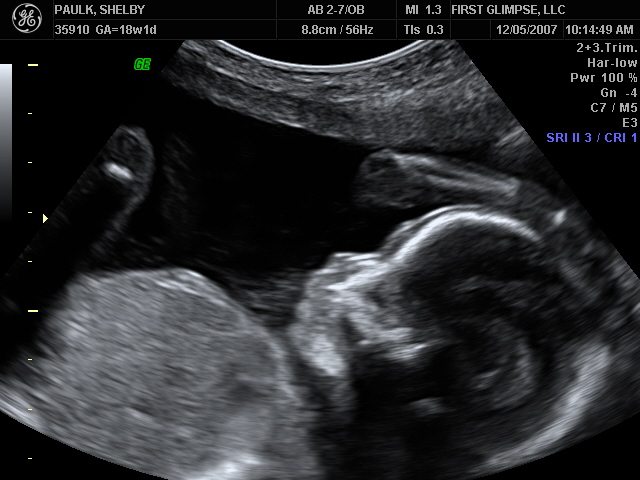

We had the ultrasound for baby number #2 on Tuesday, as we like to refer to HIM as (at least until we come up with a name, which could be a while given our track record). Yes, I said HIM…we are having a baby BOY!! We are so blessed to be have one of each. God is so good. Here are a few of the many ultrasound pictures that were taken. God has blessed us with one very healthy baby and we pray that this little guy is just as healthy. So far the docs. say everything looks great, we’ll have another ultrasound around 28 weeks because of where the placenta is located right now. It needs to move because it is blocking the cervix, but the ultrasound tech said that 9 of 1o times it will move…we pray that it does, because if it doesn’t I will have to have a C-Section.